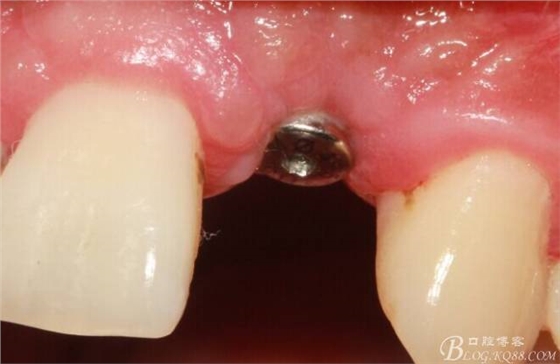

4個月后,唇側(cè)豐滿度尚可,與鄰牙之間齦乳頭完整。

保留齦乳頭翻小瓣。